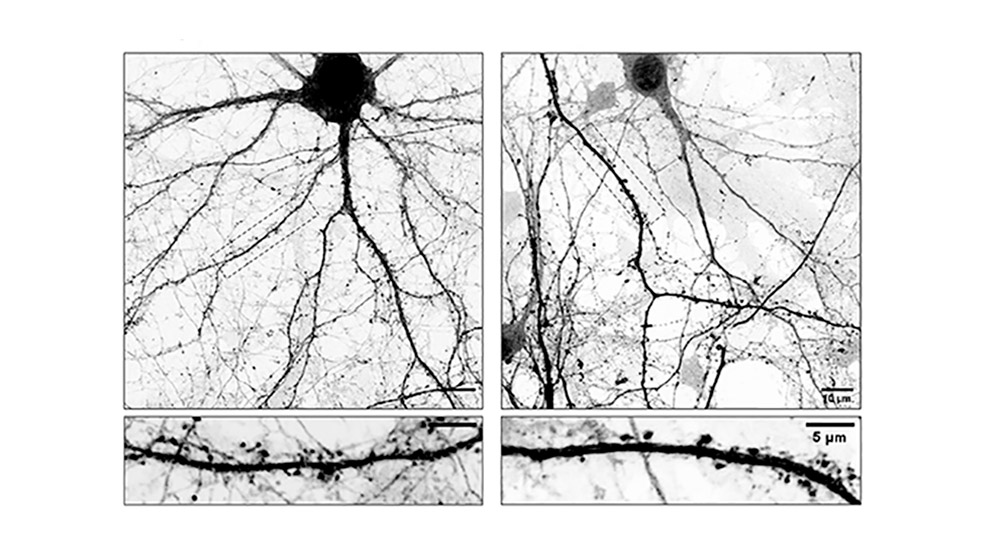

Acá es donde la cosa se pone fascinante. Las espinas dendríticas son como las «antenas» que usa la neurona para recibir señales y conectarse con otras (lo que llamamos sinapsis). Si los rieles se ponen rígidos por culpa del medicamento, los materiales no llegan a las antenas.

¿El resultado? Las neuronas pierden sus antenas. Se quedan incomunicadas. «Entendemos que esta inestabilidad sináptica podría explicar algunas de las complicaciones que aparecen luego de un tiempo prolongado de tomar L-Dopa», detalla el investigador cordobés.

- Cultivos neuronales: Usaron células de ratón que maduraron en laboratorio.

- Microscopios de alta resolución: Para ver en tiempo real cómo los «rieles» crecían o se achicaban.

- Ingeniería genética: Crearon neuronas modificadas que no podían incorporar la droga a sus microtúbulos. Ahí confirmaron la hipótesis: si la droga no se metía en el esqueleto, los efectos negativos no aparecían.